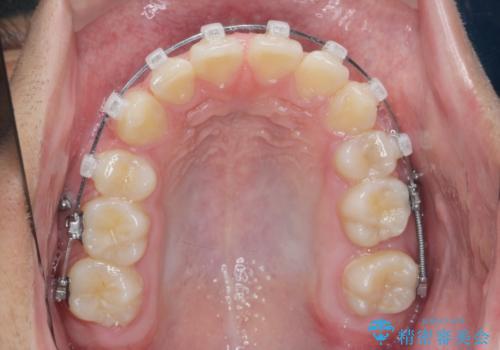

- 前歯のがたつきが原因で歯ブラシしづらい、見た目を改善したい!と矯正治療を希望され来院されました。

スペースの不足が見られるため、小臼歯の4本抜歯を行いマルチブラケットを用いた矯正治療を計画します。

噛み締めが強く、治療に時間がかかりましたが矯正治療の仕上がりに満足いただくことができました。